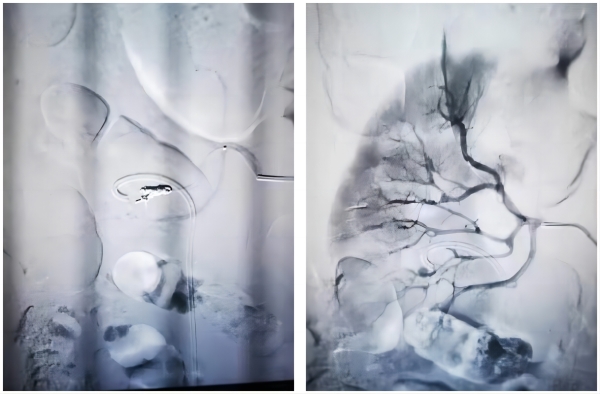

患者为60岁男性,2023年12月16日以“用力后大量肉眼血尿2小时余”代主诉就诊于阿里地区人民医院急诊科,入院时血压为60mmHg/40mmHg,出血量估计2000毫升以上。初步诊断:“失血性休克(出血原因不明),肉眼血尿,膀胱血块填塞”。急诊科抗休克治疗同时请我院泌尿外科援藏医生李钊伦急会诊进行膀胱冲洗,但患者出血速度远超血液输入速度,并且膀胱内反复出现大量血凝块填塞。患者血压难以维持,性命危在旦夕。紧急时分,由李钊伦副主任医师指挥,在极短时间内送患者进入手术室,同时通知西安交大一附院援藏医生徐高峰做好介入栓塞准备。膀胱血块清除完毕后可见右输尿管开口呈动脉式喷血,在极端条件下快速完成膀胱镜和输尿管镜检查,判断大量出血来自于右肾。随即果断决定行右肾血管造影术,结果显示:右肾中下极叶间动脉有一枚5mm大小动脉瘤,随血流冲击扩张搏动,完全可以解释出血凶险程度和休克严重程度。确认出血责任动脉瘤后对其进行了高选择式栓塞,术后患者转ICU继续治疗,目前患者已经完全苏醒,病情稳定。